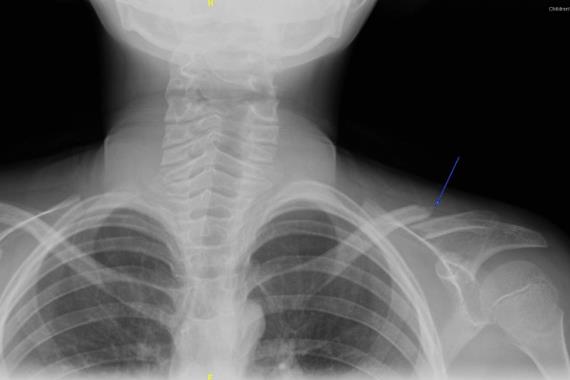

锁骨骨折还是比较容易诊断的,受伤侧肩膀低于健侧肩膀,颈部向伤侧倾斜,患侧上肢难以上举和后伸。锁骨骨折治疗包括外固定和内固定,预后良好,进行及时骨折治疗和正确术后康复锻炼即可。